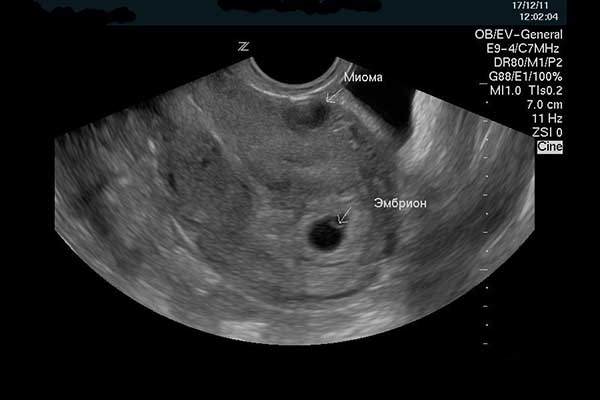

На фото ниже показана УЗИ миомы при беременности.